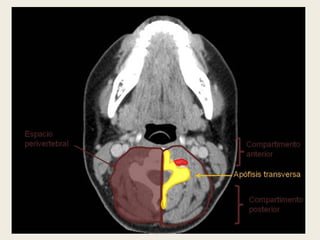

ESPACIO PERIVERTEBRAL.

 En gran parte de la literatura radiológica de

consulta, el espacio perivertebral se denomina

espacio prevertebral.

 Se ha cambiado el nombre debido a que el espacio

por detrás de la capa profunda de la fascia

cervical profunda sólo es verdaderamente

prevertebral en su parte anterior. Queda definido

propiamente por la capa profunda de la fascia

cervical profunda, que recubre la musculatura

prevertebral y paravertebral posterior, y se

inserta en las apófisis transversas de las

vértebras.

 Contiene elementos del plexo braquial, el nervio

frénico, la musculatura pre y paravertebral, los

cuerpos vertebrales, las arterias y venas vertebrales, y

el cordón medular.

ESPACIO PERIVERTEBRAL

 Queda definido por la capa profunda de la fascia

cervical profunda y envuelve la musculatura

inserta en las apófisis transversas.

 El espacio perivertebral contiene elementos del

plexo braquial, el nervio frénico, los músculos

prevertebrales, paravertebrales posteriores y

escalenos, las arterias y venas vertebrales, los

cuerpos vertebrales y el cordón medular.